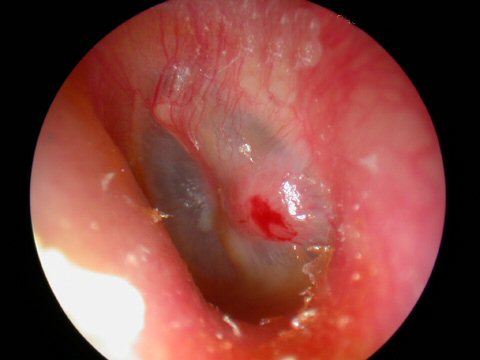

Acute Infection with bulging of the tympanic membrane due to pressure from purulence (pus) behind it. The last picture reveals an ear tube that has gotten prematurely blocked and the ear is once again infected.